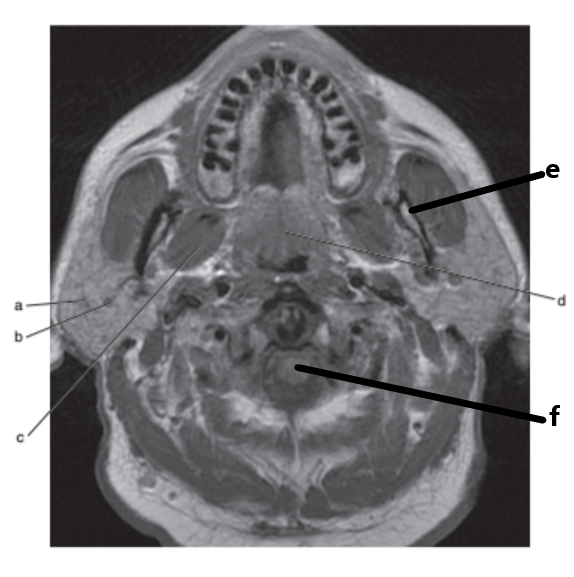

What imaging plane is this ?

transverse

What anatomy is letter b ?

Epiglottis

Soft palate

Masseter muscle

Mandible

Parotid gland